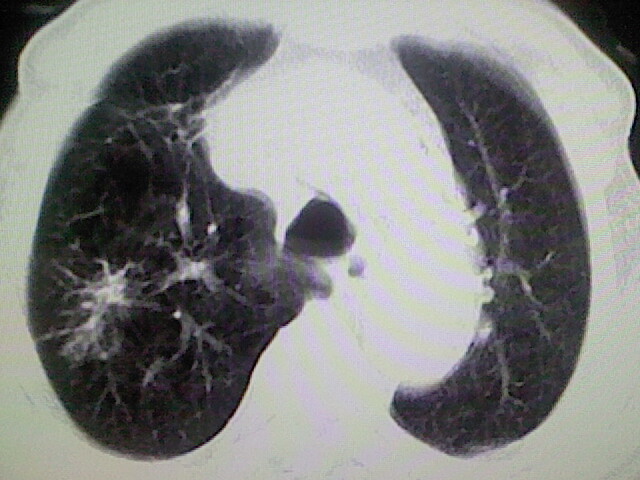

以下是引用zsl6918在2008-8-28 16:49:00的发言:[br]双肺炎性病灶,食管狭窄估计与心房增大压迫所致。

以下是引用xulianj在2008-8-28 20:36:00的发言:[br]慢支肺气肿伴感染,右上肺陈旧性结核;食道建议胃镜检查。

以下是引用wqs571018在2008-8-28 21:18:00的发言:[br]慢支继发感染,右上肺陈旧性结核;食道建议胃镜检查。